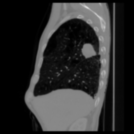

Aside from quantitative results, we provide a principal component analysis (PCA) of the embeddings of Merlin, CT-FM, CT-CLIP, and our COLIPRI encoders, on a lung cancer case from the MSD Lung dataset (Fig. 6).

The resolution of the embeddings of Merlin and CT-FM is very low, providing hardly any localisation of semantics. CT-CLIP yields embeddings of higher resolution, allowing one to map the features from the input chest CT to the PCA map. However, the PCA is inconsistent and noisy, and shows high sensitivity to air in its principal components, and a strong bias towards position embeddings. On the other hand, our COLIPRI encoders yield higher-resolution embeddings, which are sharper and more consistent, allowing for clear recognition of the boundaries of the patient, lungs, and the abdominal organs, as well as the lung mass present in the right lung (on the left-hand side of the coronal and axial slice views).